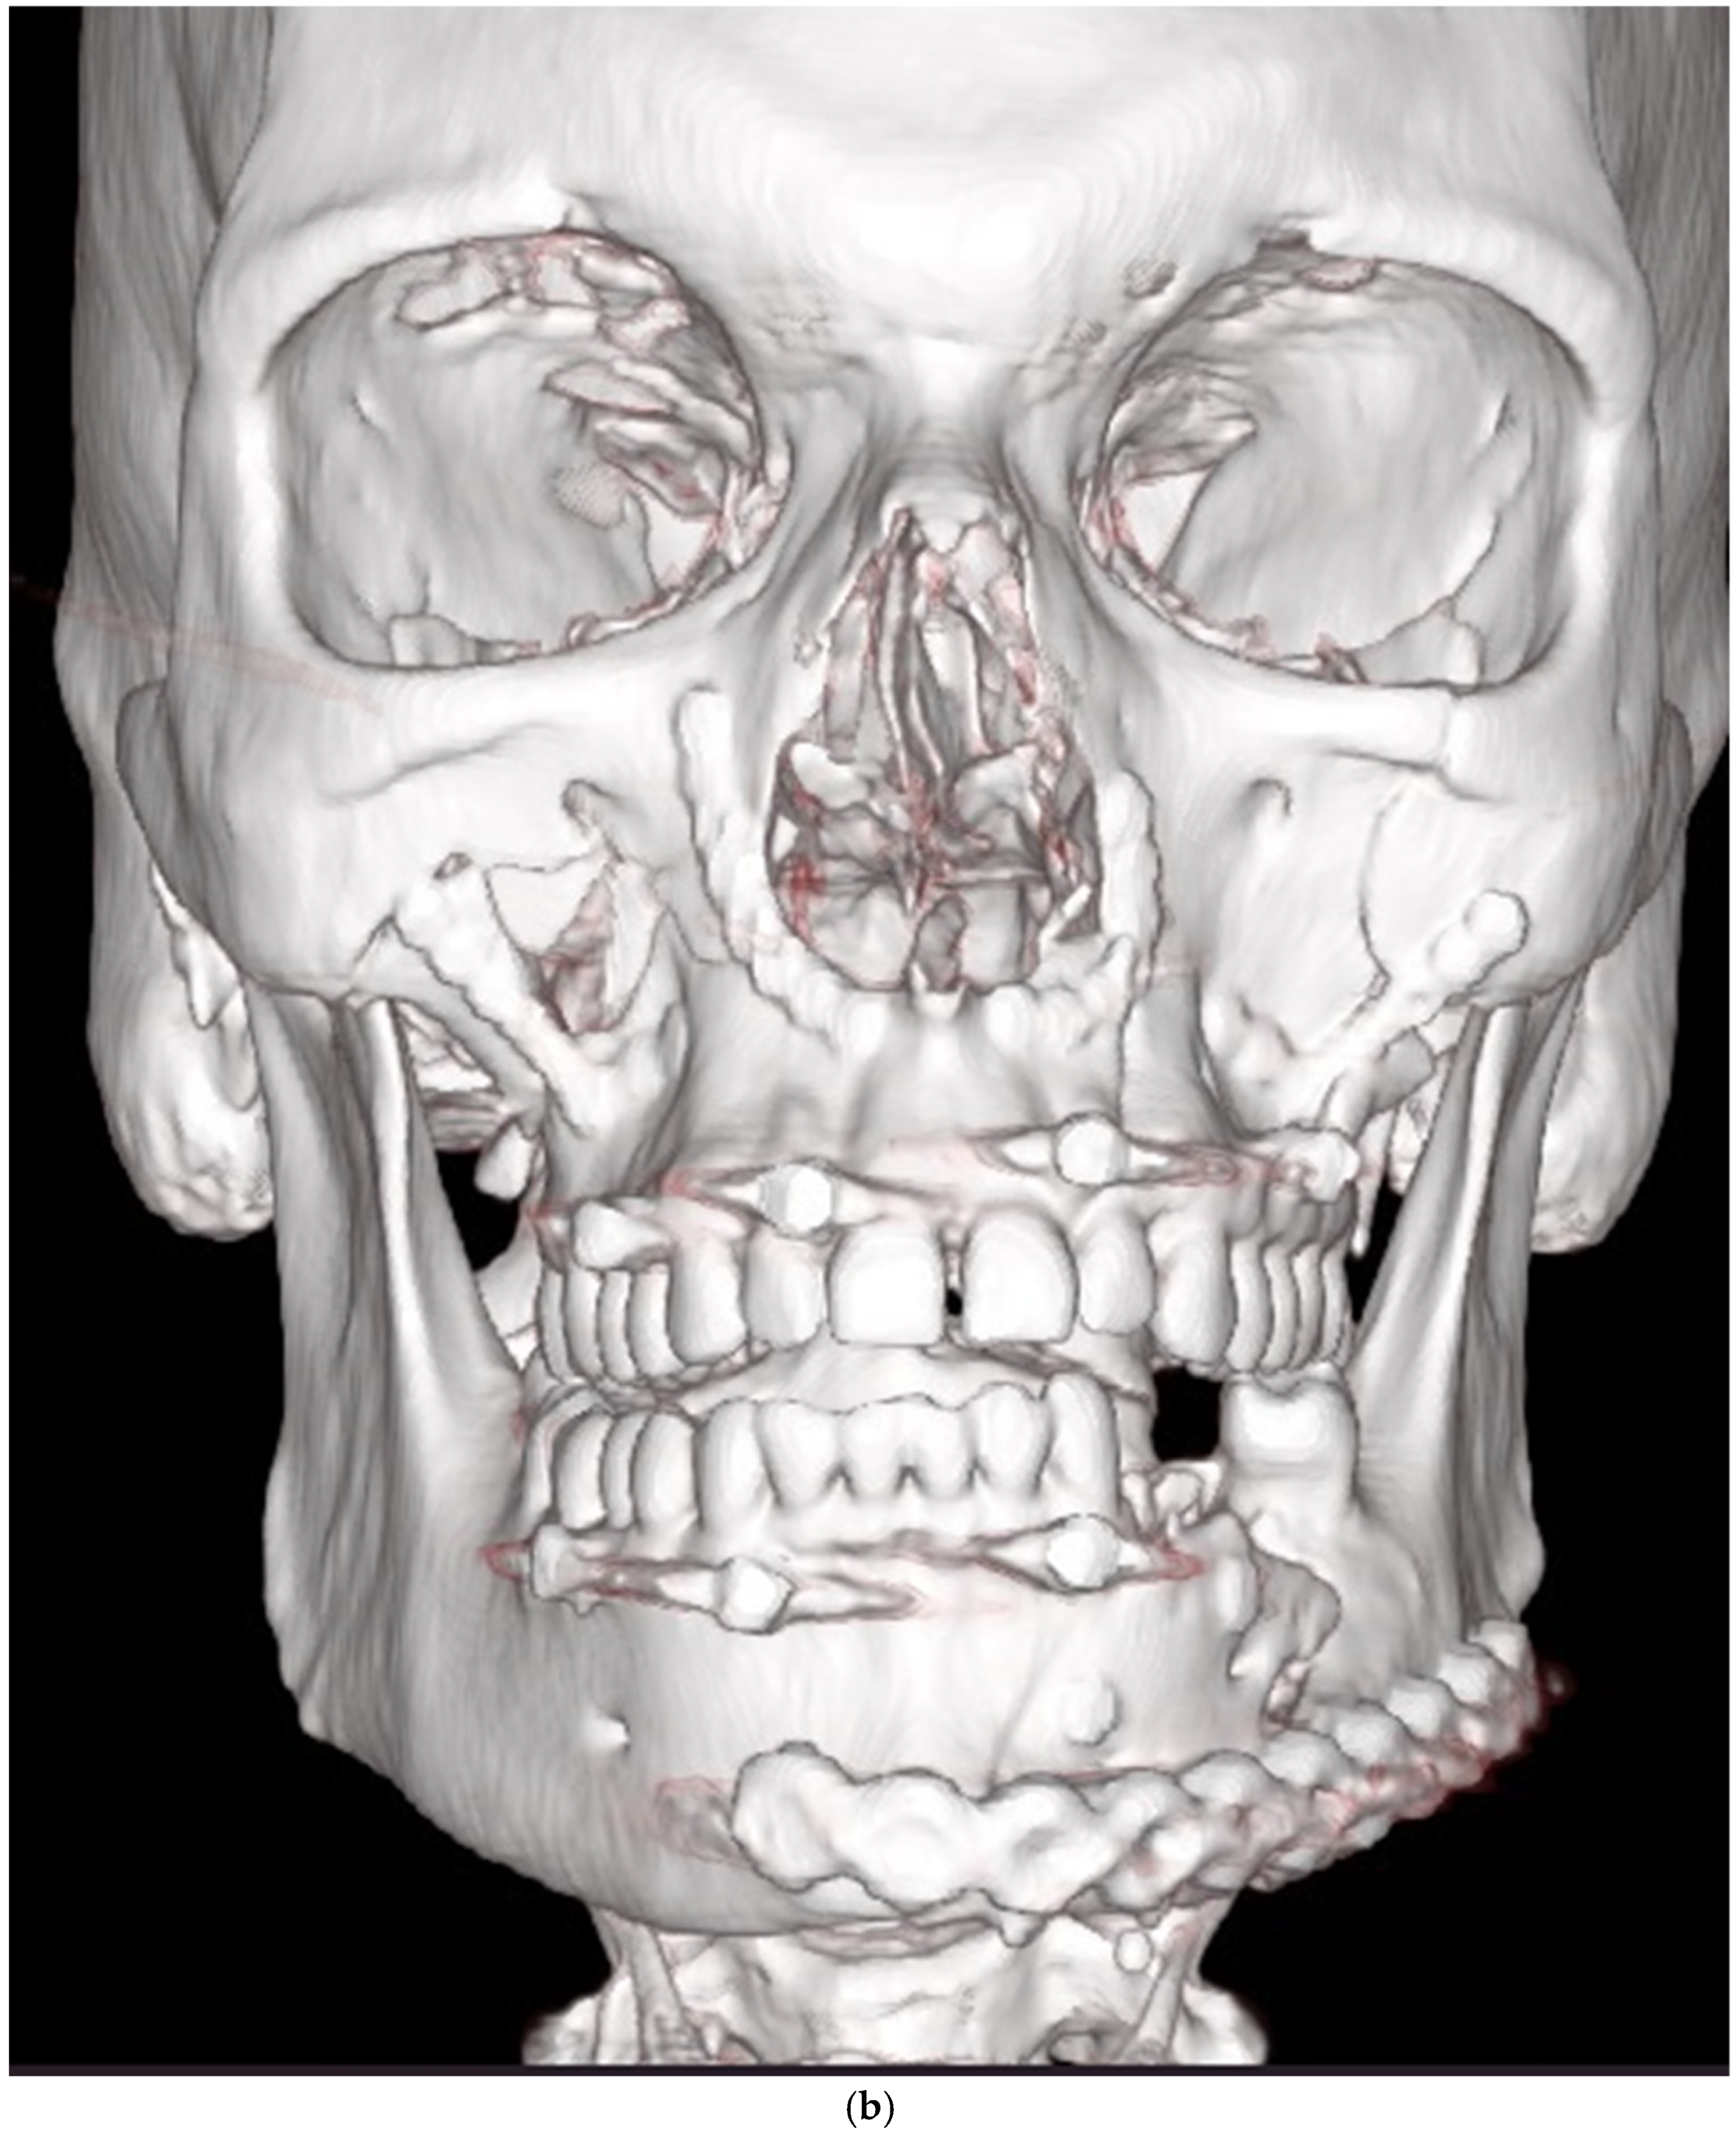

| Fractures needing redo surgery | |||||

| Mandible | 13 | ||||

| Anterior part (symphysis/parasymphysis) | 5 | 2 | 3 inadequate reductions, 2 nonunions with infection | ||

| Angle | 3 | 2 | 1 inadequate reduction, 1 infection, 1 nonunion with infection | ||

| Body | 3 | 0 | 3 inadequate reductions | ||

| Condyle | 3 | 1 | 2 inadequate reductions, 1 broken plate | ||

| Midface | 13 | ||||

| Zygomatico–orbital complex * | 6 | 4 | 6 inadequate reductions | ||

| Le Fort ** | 4 | 1 (Le Fort III) | 4 inadequate reductions | ||

| Orbit | 4 | 0 | 3 inadequate reconstructions of orbital floor fractures, 1 orbital deformity due to inadequate reduction of the zygomatic bone | ||